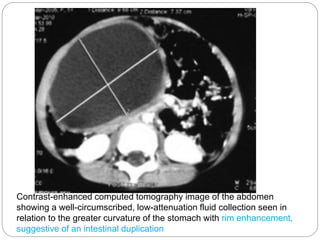

Diagnosis of Multiple Gastric Duplication Cysts

Causing Gastric Outlet Obstruction in a Pediatric

Patient

Contrast-enhanced computed tomography image of the abdomen

showing a well-circumscribed, low-attenuation fluid collection seen in

relation to the greater curvature of the stomach with rim enhancement,

suggestive of an intestinal duplication